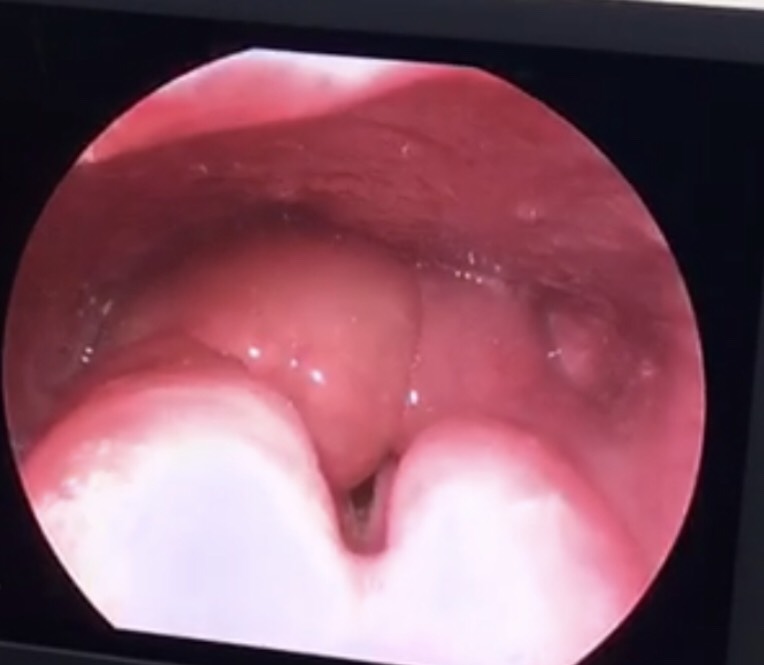

viem nap thanh nhiet Hình ảnh sau khi phẫu thuật

3 ngày sau phẫu thuật, bệnh nhân được rút canuyn và tình trạng sụn nắp đã được cải thiện rất nhiều. Bệnh nhân được điều trị kháng sinh phối hợp, tiêm và truyền kết hợp với chăm sóc đường thở tại chỗ. Hiện tại sức khỏe của bệnh nhân hoàn toàn hồi phục.